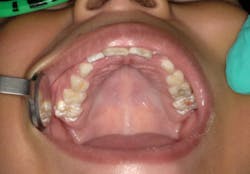

Advantage Arrest was cleared as a medical device in 2014 for the treatment of dentinal hypersensitivity, the same clearance given to 2.5% and 5% sodium fluoride varnish. It is being used off-label in the US for arresting and preventing caries in children and adults.

In 2016, Advantage Arrest was the first oral care product to receive the FDA’s Breakthrough Therapy Designation (BTD) for the arrest of tooth decay in children and adults. BTD represents the FDA’s effort to address an unmet, serious, and life-threatening medical need where there is no available therapy.

In use for more than 50 years as a caries-arresting drug in Japan and other countries, the silver diamine fluoride (SDF) designation was granted based on the FDA review of 10 worldwide randomized clinical trials evaluating silver diamine fluoride for caries arrest in children aged 3 to 9 or adults aged 60 to 89, as well as studies conducted by Advantage Silver Dental Arrest LLC. Collectively these trials involved approximately 1,500 subjects who were monitored for 1 to 3 years.